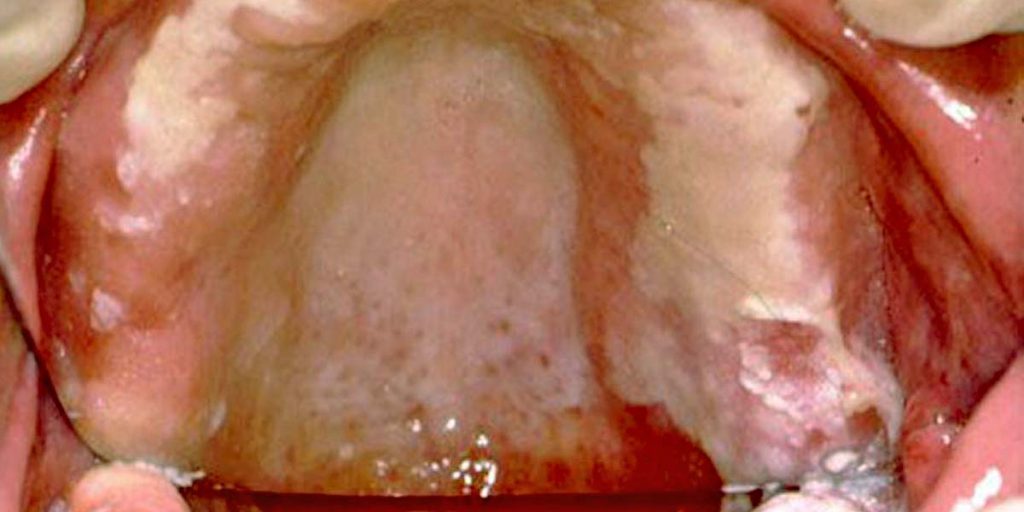

A fogászati fémallergia tünetei – sokszor megtévesztők

A tünetek sokfélék lehetnek, és gyakran nem köthetők azonnal a fogászati kezeléshez. A leggyakoribb panaszok:

— a szájnyálkahártya irritációja vagy fekélyesedése,

— ínyvérzés vagy az íny duzzanata,

— parodontális gyulladás,

A tünetek sokszor nem egyértelműek, ezért gyakran hosszú idő telik el, mire a páciens és az orvos felismeri, hogy a háttérben fémallergia áll. A probléma megszüntetésének egyetlen hatékony módja az allergiát kiváltó fém eltávolítása.